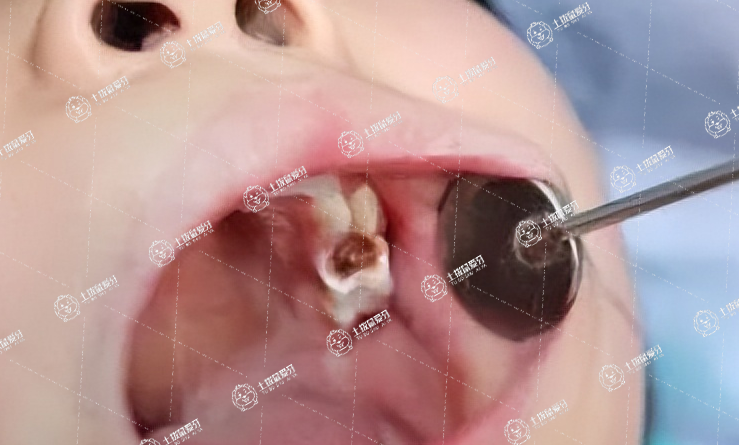

相信不少人有過(guò)這樣的經(jīng)歷,牙痛不是病,但是疼起來(lái)要人命。有時(shí)候,真心疼起來(lái)讓人懷疑人生,去醫(yī)院檢查發(fā)現(xiàn)是齲齒,齲齒進(jìn)一步的壞掉后就需要牙友們及時(shí)做補(bǔ)牙處理。補(bǔ)牙過(guò)程要多久時(shí)間?這或許是牙友們比較在意的事情,接下來(lái),我們一起來(lái)了解一下!

補(bǔ)牙大概需要30-120分鐘,需要根據(jù)牙齒的損壞程度來(lái)決定時(shí)間長(zhǎng)短。

當(dāng)蛀牙的情況不嚴(yán)重時(shí),補(bǔ)牙的過(guò)程會(huì)比較快,大概30分鐘就能完成。

蛀牙情況嚴(yán)重,出現(xiàn)牙髓外露或感染時(shí),還需做根管治療,這種情況下花費(fèi)的時(shí)間及復(fù)診次數(shù)會(huì)更多。

牙齒有輕微蛀牙并且沒(méi)有露出牙髓時(shí),需將牙齒齲洞周圍清理干凈,再用特殊的材料進(jìn)行填補(bǔ),整個(gè)過(guò)程花費(fèi)時(shí)間不多,在半個(gè)小時(shí)到一個(gè)小時(shí)之間。

牙齒損壞程度嚴(yán)重,需要進(jìn)行根管治療時(shí),一般需要做3-5次,所需時(shí)間在一個(gè)月到三個(gè)月。

所以牙齒出現(xiàn)齲洞時(shí),患者應(yīng)及時(shí)處理,避免蛀牙發(fā)展到后期導(dǎo)致?lián)p壞牙髓。在補(bǔ)牙后要注意不要咀嚼較硬的食物,以防止補(bǔ)牙材料脫落。